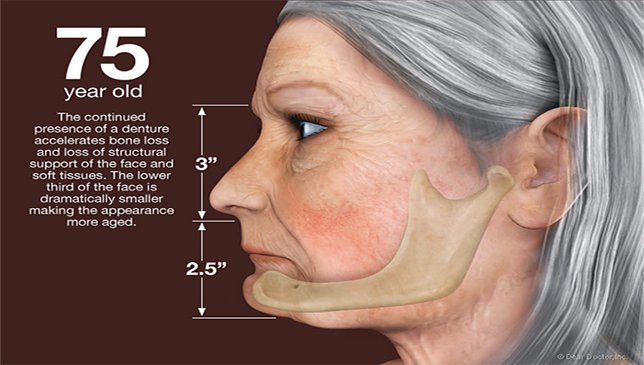

Diş kaybının gizli sonuçları Modern diş hekimliğinin amacı, eksik dişleri olan bireylere normal ve sağlıklı fonksiyon, konfor, estetik, konuşmayı geri kazandırmaktır. Nüfusumuzun…